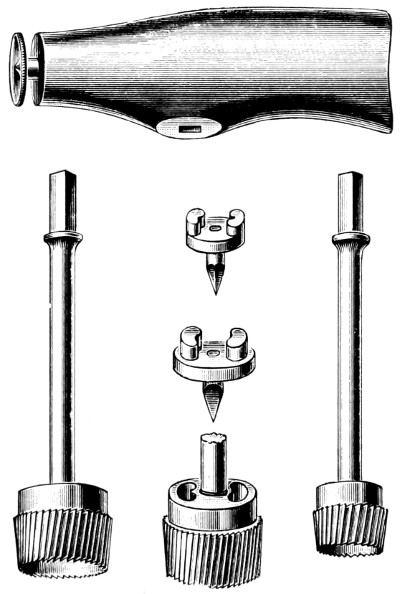

| 7. Hudson’s trephine | 20 |

| 8. The hand-trephine | 21 |

| 9 and 10. The technique of trephining | 22 |

| 11-16. Instruments used in trephining | 23, 24 |

Fig. 7. Hudson’s Trephine. Showing the usual method of using the spiral perforator, spiral follower, and enlarging burr.

Hudson’s trephine is shaped after the style of the carpenter’s brace and is fitted with three cutting heads—the perforator, the follower, and the enlarging burr. It is claimed that injury to the dura and brain is impossible, the instrument becoming automatically locked so soon as the resistance of the internal table is overcome, a thin film of bone being pushed in front of the advancing head. I have had the opportunity of using this instrument, and so far as my experience goes it answers all requirements. Still, I prefer the ordinary hand-trephine so long as it satisfies certain requirements. It must be of simple mechanism and strong, the handle of good size and shaped to fit the hand, the shaft and head so interlocked as to allow of no independent movement, and the hollow head sharply toothed and bevelled externally, in continuity with the teeth, for a distance of half an inch. The bevelling is so arranged that the actual cutting process is only effected during supination of the hand and forearm. The pin of the trephine should not project beyond the cutting edge for a greater distance than about ·2cm. This pin should be readily removable.

Fig. 8. The Hand-trephine.

The pattern which I am accustomed to use is depicted in Fig. 8. The trephines are kept in three sizes—diameter 1⁄2, 1, and 11⁄2 inches. The intermediate size is used for ordinary trephining, the small one for the formation of the osteoplastic flap, the large for the removal of a disk of bone which includes within its circumference the area involved in some depressed and punctured fractures (see p. 133).

Fig. 11. Horsley’s Disk or Bone Elevator.

Fig. 12. Horsley’s Dural Separator.

Fig. 13. Keen-Hoffmann’s Craniectomy Forceps.

Fig. 14.

Lane’s Fulcrum

Craniectomy Forceps.

Fig. 15.

Horsley’s Gouge

Forceps.

Fig. 16. De Vilbiss’s Craniectomy Forceps.

Previous to any attempt at enlargement of the trephine hole, the dura mater must be separated from the bone with the aid of Horsley’s dural separator or other suitable instrument. Of the many patterns of craniectomy forceps, the following will be found to suit all requirements:—

The visceral blade is introduced between the dura and the bone and ‘morcellement’ carried out. It is essential[25] that the surgeon should not be too greedy, resting content with the removal of small fragments at a time.

They possess great mechanical advantage and are mainly suited for the rapid removal of large portions of bone.

This instrument is mainly utilized in the smoothing and refreshing of sharp edges of bone, and in the ‘morcellement’ of the thinner portions of the skull—temporal and cerebellar regions.

A clever contrivance whereby the operator is enabled to cut a narrow channel in the bone. Mainly utilized in the formation of the osteoplastic flap.